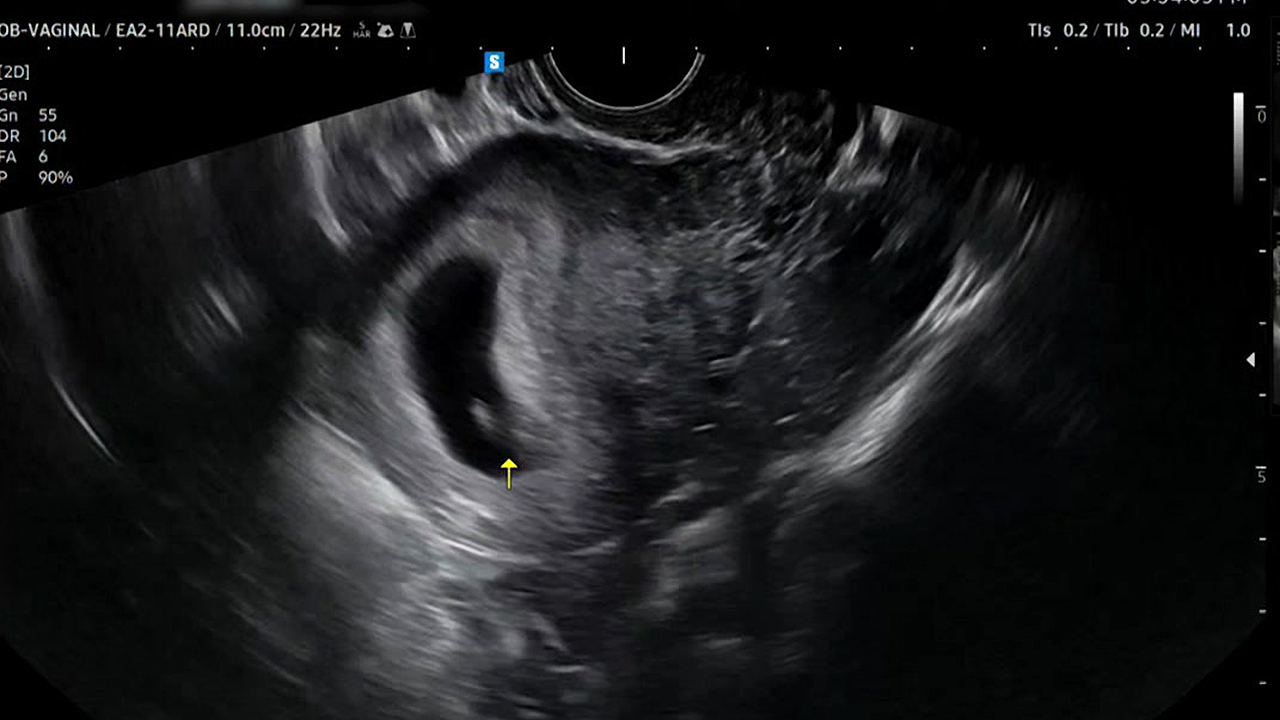

[사건X파일] 멀쩡한 태아 "긁어내라" 오진…아기 잃을 뻔한 부부